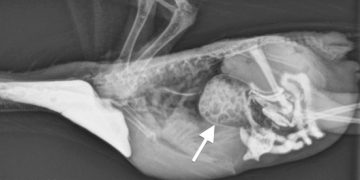

Evcil kuşlarda çinko zehirlenmesi (toksikozu). Çinko evcil kuşlar için birçok enzim fonksiyonu, deri sağlığı ve fertilite gibi çeşitli amaçlar için ...